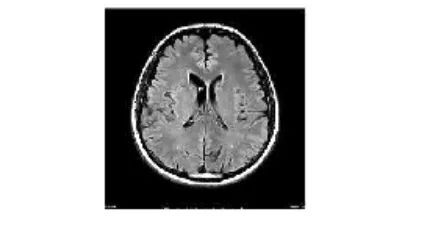

使用深度学习进行预测

为了通过我们的模型对一批样本图像进行预测,在开始分析之前我们需要做以下工作流程:首先将待预测的图像导入系统中;接着对这些图像应用归一化处理以便于后续分析;最后生成标准化的数据格式并基于这些预处理后的数据特征进行预测以提高其稳定性。

image = Image.open("image(2).jpg")

display(image)

在其中,我们运用了 matplotlib 的 imshow 函数来呈现图像内容,并借助 Python Imaging Library (PIL) 来完成各类图像处理任务。该库中的 ImageOps 模块专门支持多种成像功能及相关的预处理操作。

现在我们将使用我们的 CNN 模型预测上述图像的类别,即肿瘤类型。

经过分析, 我们确定归一化后得到的图像分类结果为第二类, 未发现肿瘤. 这与预期结果一致.

print("There's {:.2f} percent probability that the person has No Tumor".format(prediction[0][2]*100))

There's 100.00 percent probability that the person has No Tumor

借助这一方法,我们可以明确地表明我们的CNN模型能够达到最高准确度,并且在预测各种类型的脑肿瘤数据时表现最佳。因此,你可以将上述任何脑 tumor 数据集输入到基于该架构设计的 model 中进行分析。